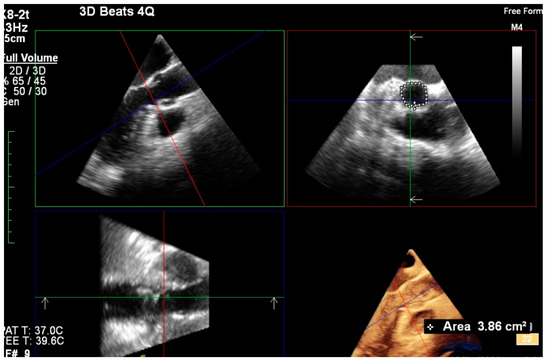

3D TEE imaging (Figure 2) was used to measure aortic annular diameters and determine the correlation of its results with those derived from MDCT imaging.

Figure 2.

Assessment of aortic annular plane via 3D TEE imaging.